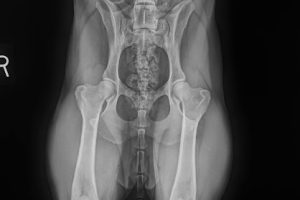

April 20, 2025 By Paige Adams, DVM Hip Dysplasia is an abnormal formation of the hip socket that can cause osteoarthritis of the joints which leads to pain and …